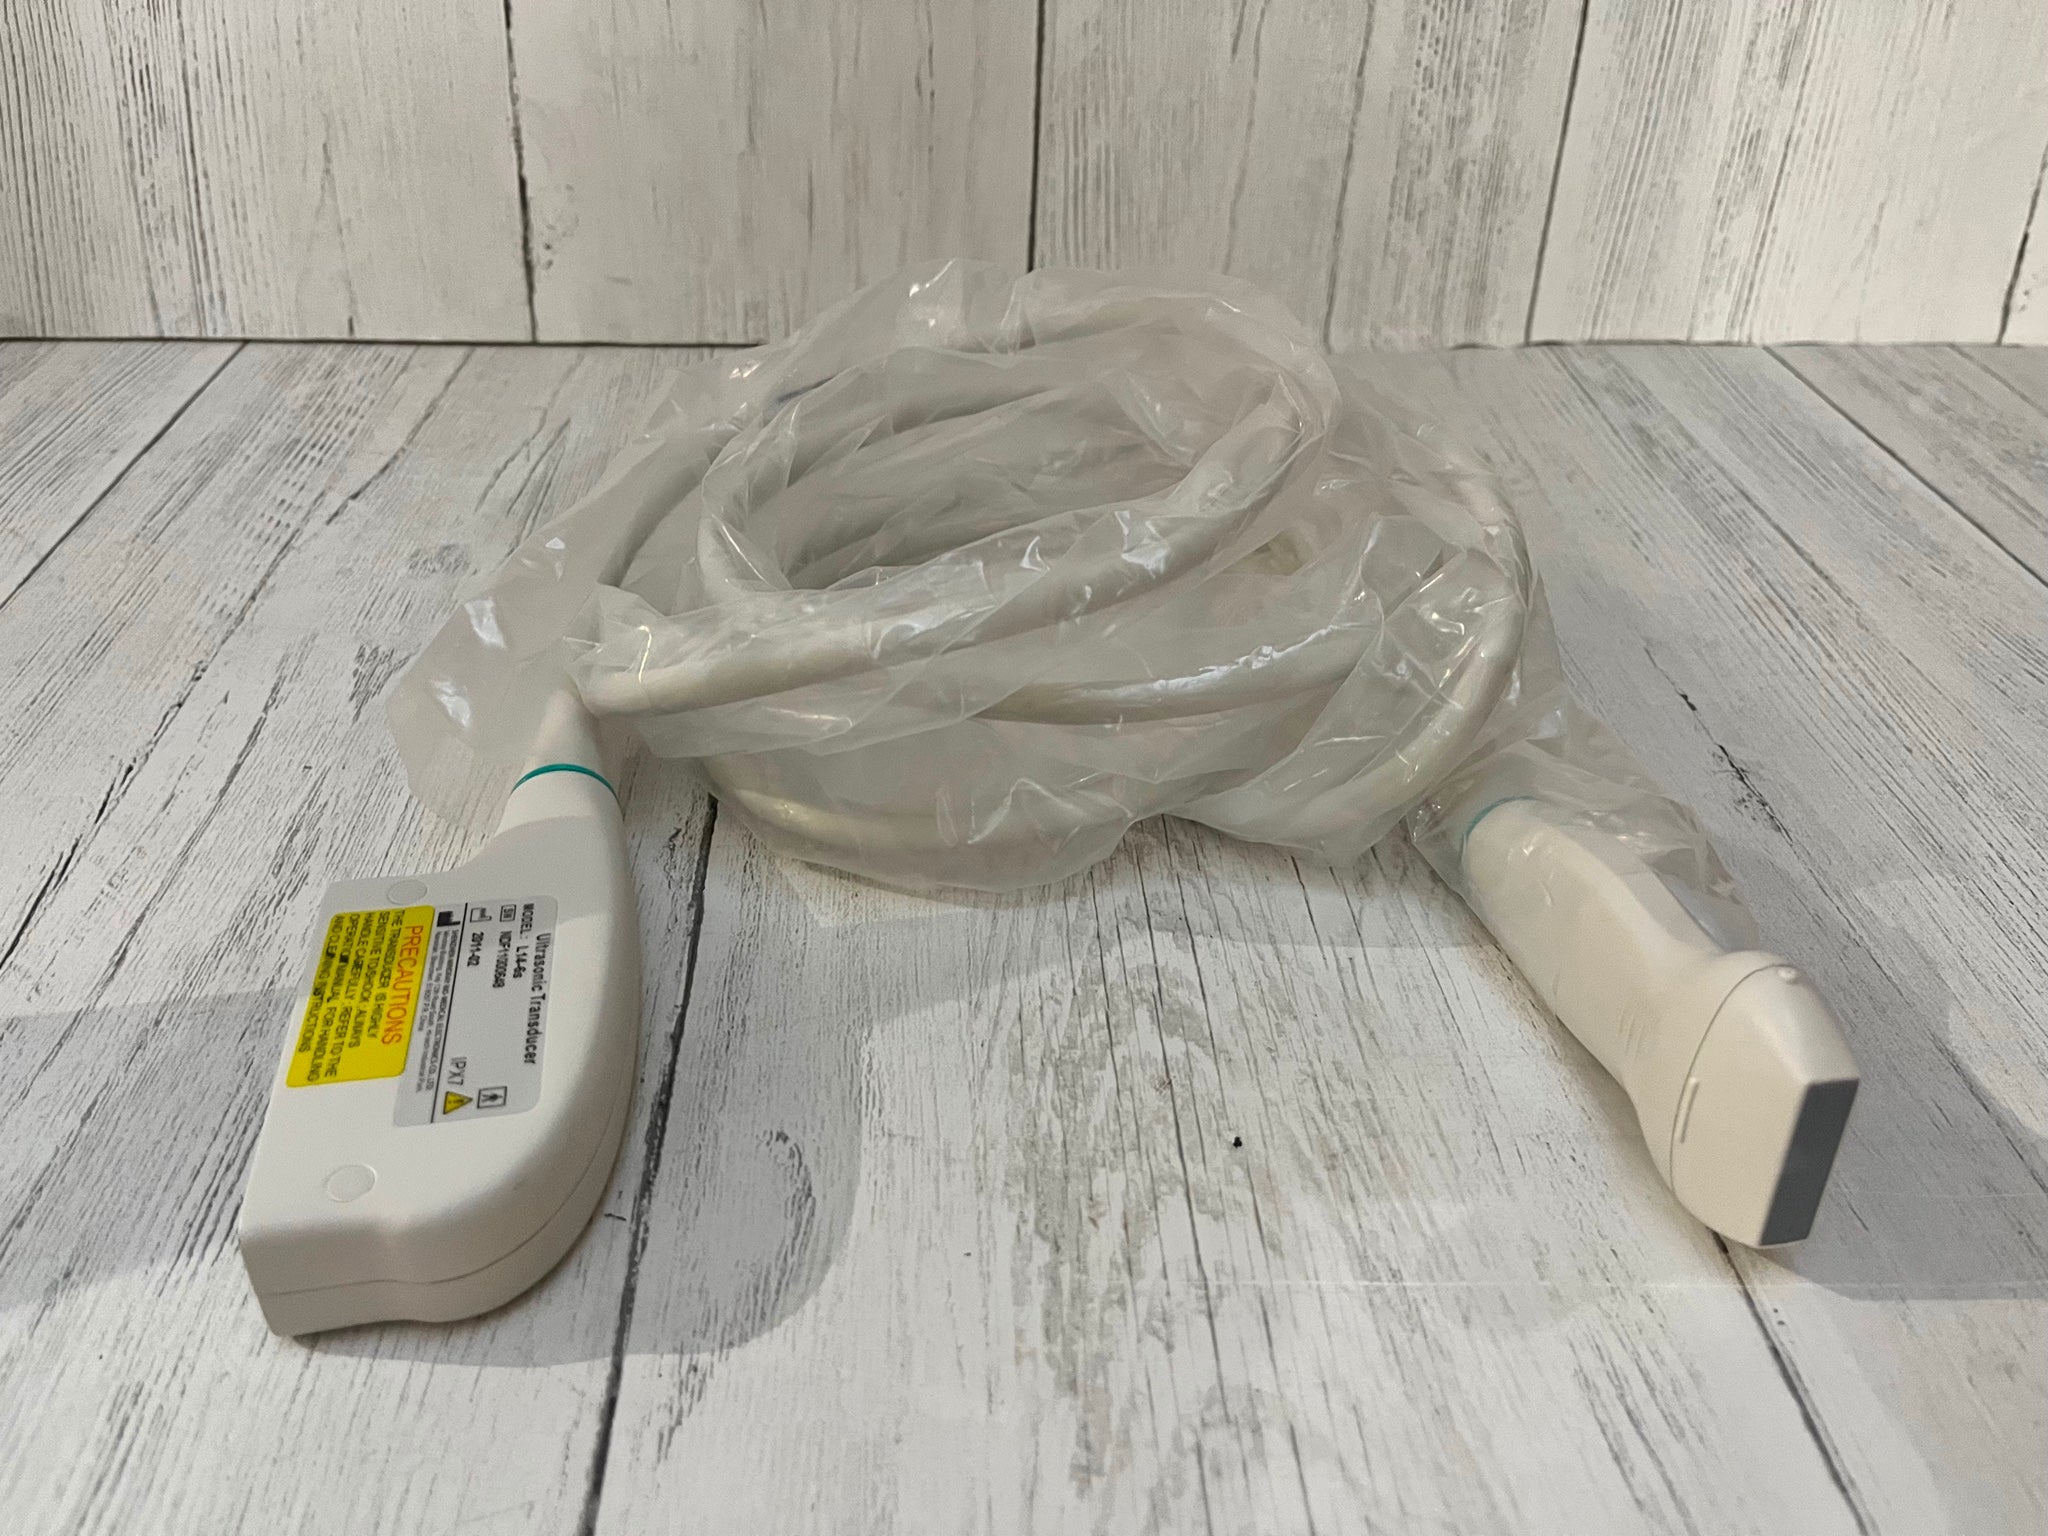

The SONOSITE TITAN OB/GYN ultrasound offers state-of-the-art imaging technology. This device uses advanced algorithms to provide clear, high-resolution images. It includes two probes: a 1-C60 convex and a 1-ICT transvaginal probe, ensuring versatility in different obstetric and gynecological applications. Because of its compact design, the SONOSITE TITAN is perfect for both hospital and remote settings, making it an ideal choice for healthcare providers.